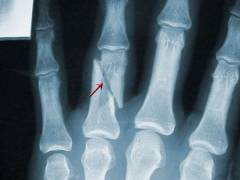

Рентгенография

Рентгенография — эффективный метод диагностики, сочетающий доступность и информативность. При правильной интерпретации снимков можно различить боли, вызванные травмами или остеомиелитом, от других причин.

При подозрении на туберкулезный артрит рекомендуется рентгенография грудной клетки. Для подтверждения реактивного артрита при неспецифическом язвенном колите целесообразно выполнить ирригоскопию (рентгеноскопию толстого кишечника с контрастом).